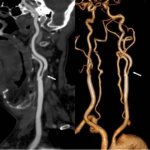

Ultrasound of head and neck vessels

Ultrasound of the vessels of the head and neck is a common diagnostic method that does not require special preparation. It takes about 20 minutes and the result is given by the ultrasound doctor immediately after the procedure.

The method allows you to assess the condition of the inner wall of the vessel, the speed of blood flow and makes it possible to conduct functional tests. Most often it is used to identify developmental anomalies, the presence of atherosclerotic plaques leading to narrowing of their lumen, the presence of external compression, including intervertebral hernias or deformed vertebrae. Ultrasound results complement MRI.